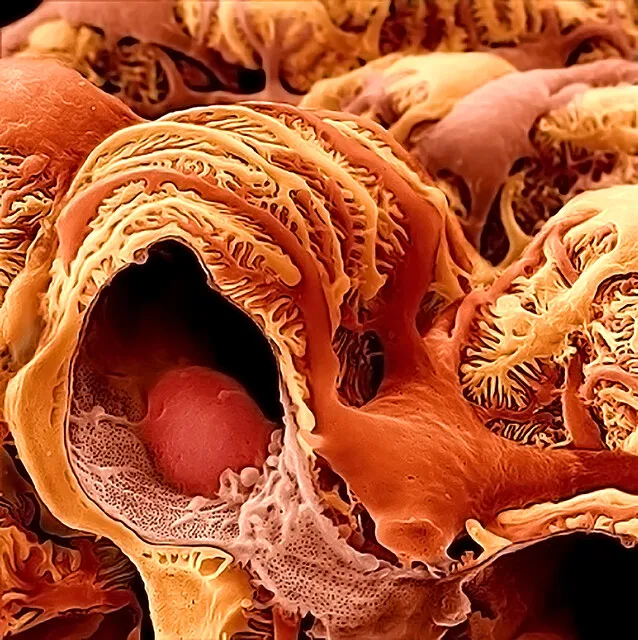

Este vídeo apresenta, de forma didática e baseada em evidências, os principais achados da tese de doutorado sobre amiloidose renal, com foco em proteômica glomerular e ativação do complemento. São discutidos aspectos diagnósticos, implicações fisiopatológicas e correlações clínico-patológicas relevantes para a prática do nefrologista. O conteúdo sintetiza dados inéditos de matriz extracelular glomerular e diferencia perfis entre subtipos de amiloidose. Trata-se de um material aprofundado e acessível, ideal para atualização de especialistas na área.